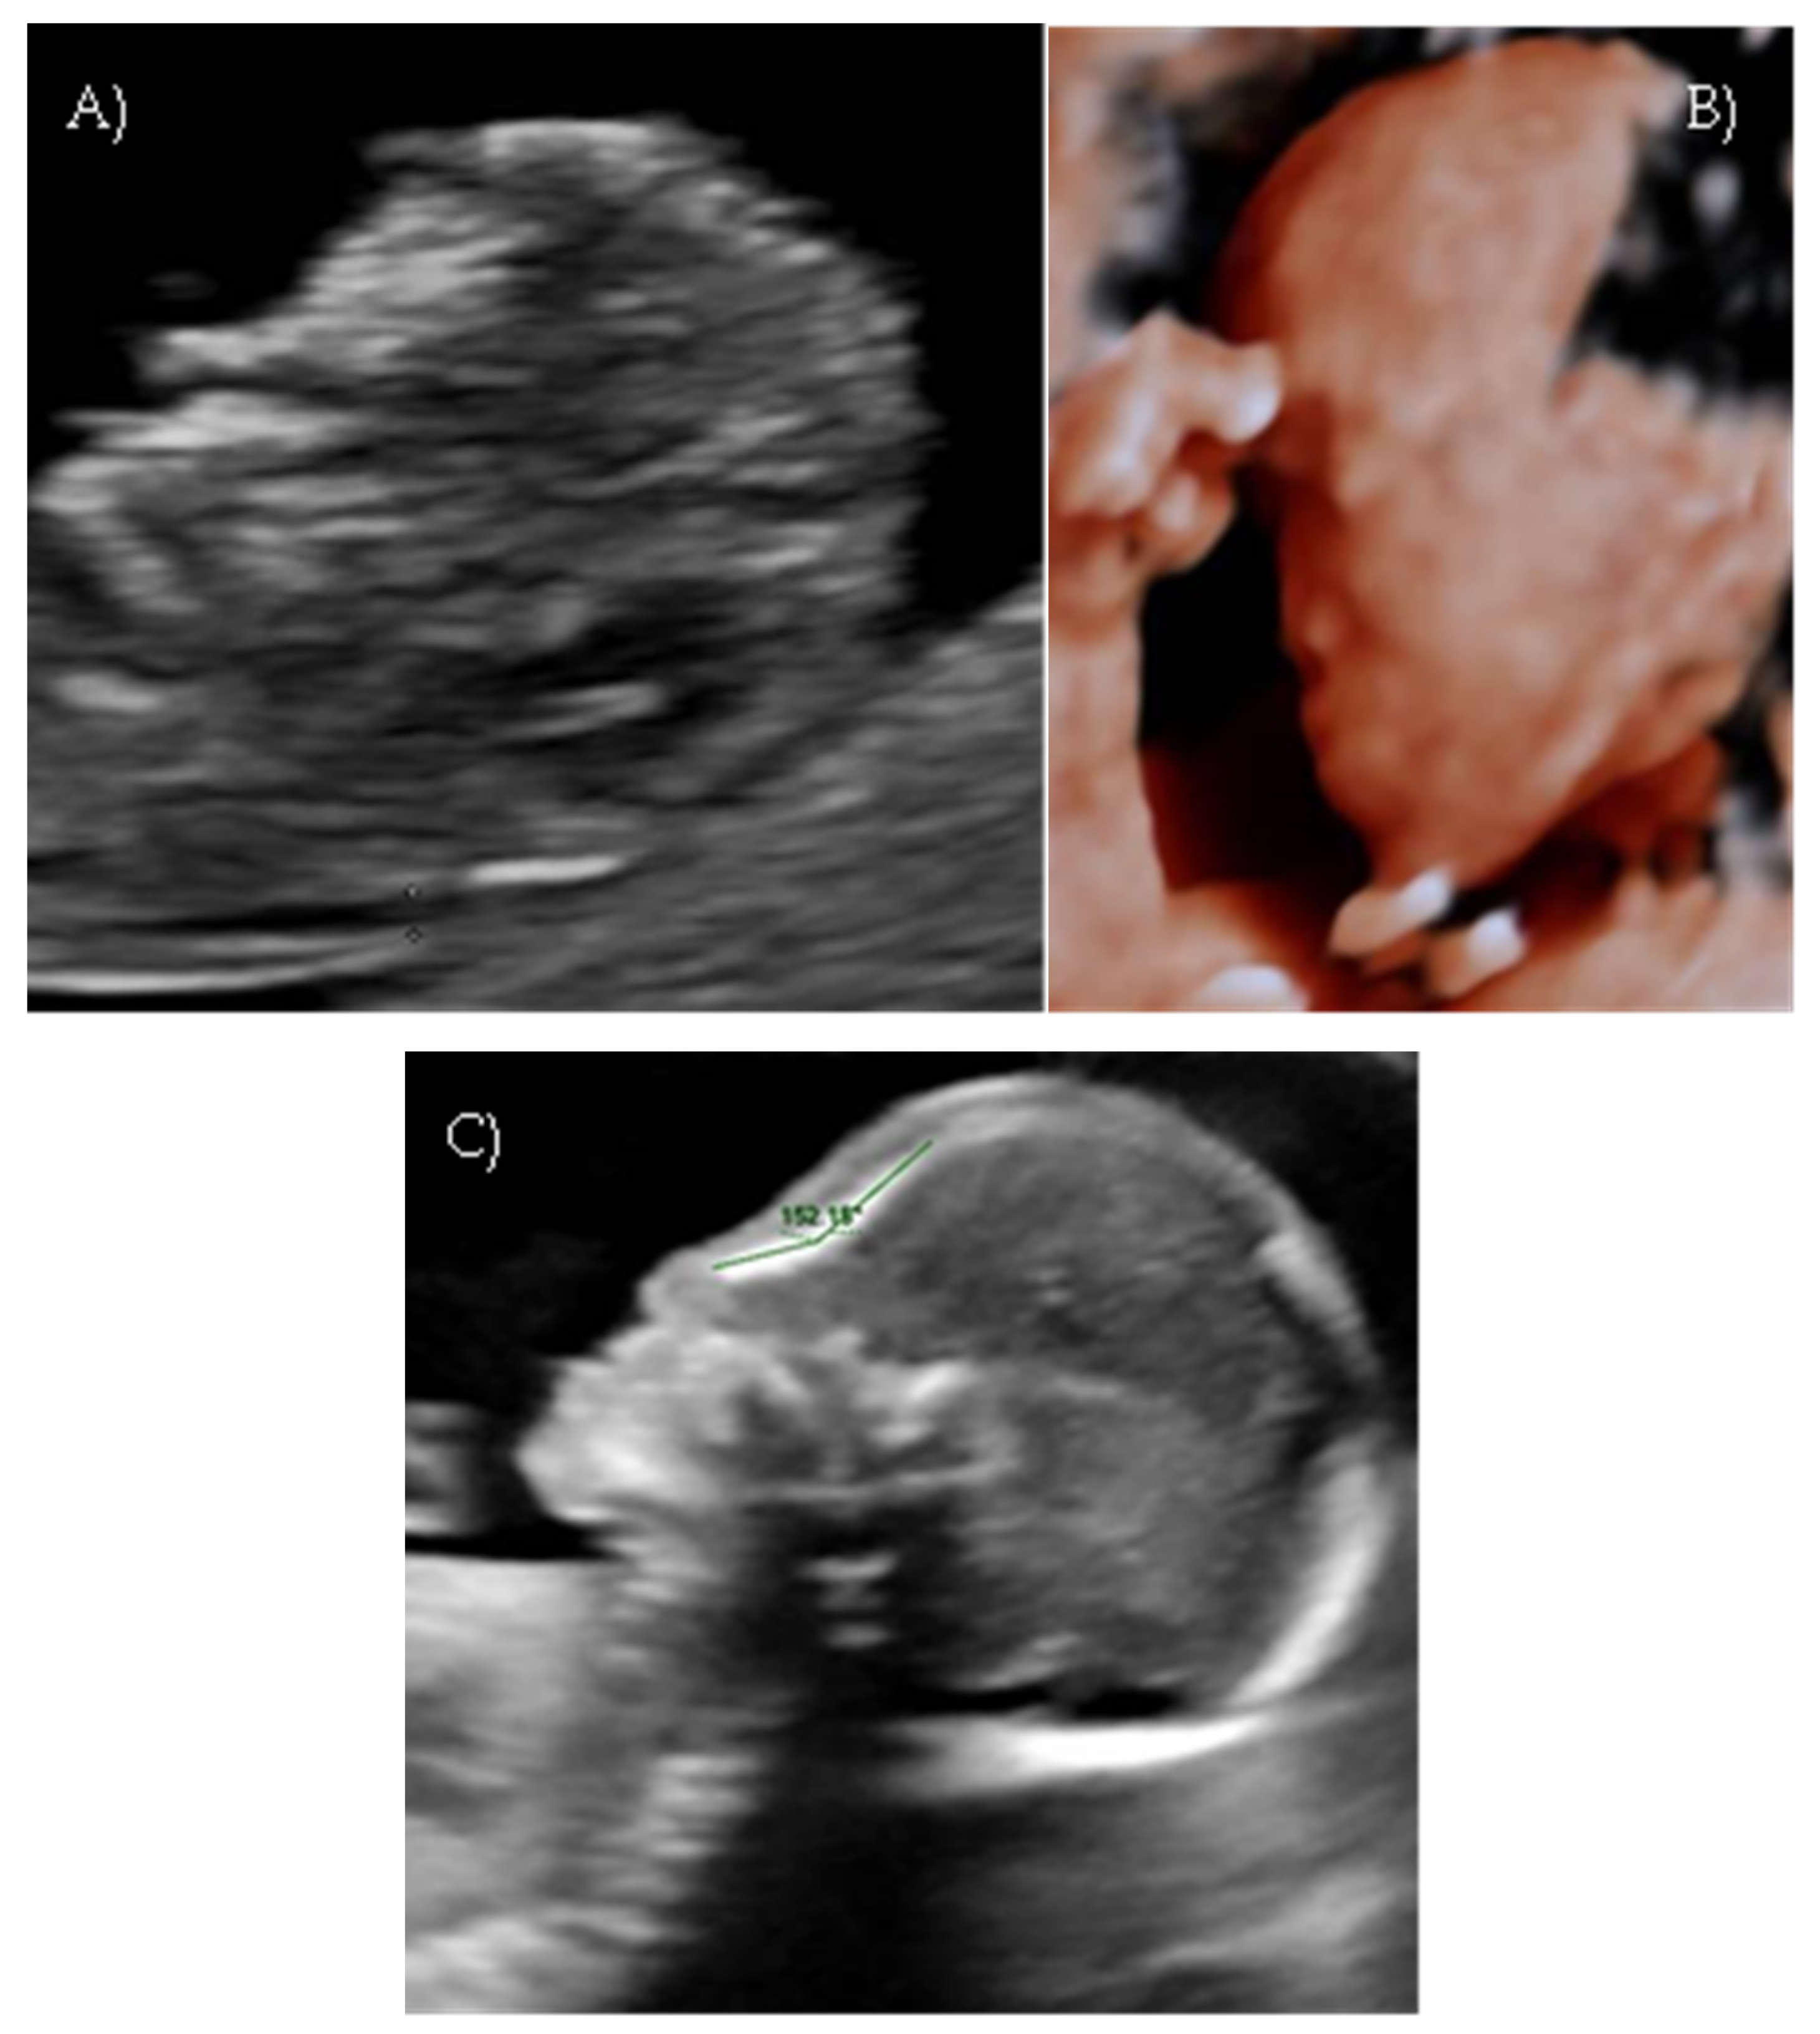

Her first-trimester combined screening for aneuploidies was low risk for trisomy 21, 18, and 13, and preterm preeclampsia. The nuchal translucency was within normal ranges (Figure 1A).

A detailed ultrasound scan was performed at 21 weeks and 1 day of gestation at our fetal medicine unit. Nasofrontal angle, nasal bone, and maxillary width were measured and compared to published references to unaffected fetuses at similar gestational ages [12,13]. Facial dysmorphism was further investigated by 3D scan (Figure 1B) through multiplanar mode and surface rendering, which allowed a more realistic representation of the fetal face, thus allowing characterization of the defect.

A flattened fetal facial profile with a nasal-frontal angle of 152.18° (cut-off: <143°, [14]), consistent with Binder-type maxillonasal dysplasia, was confirmed. To identify any other structural abnormalities, detailed examinations of the fetal anatomy and a fetal echocardiogram were conducted. No additional structural anomalies were identified (Figure 1C).

Figure 1. Case 1. (A) First-trimester 2D ultrasound Fetal profile. (B) Flat fetal profile, 21 weeks and 1 day, 3D reconstruction. (C) Nasal-frontal angle: 152.18°.